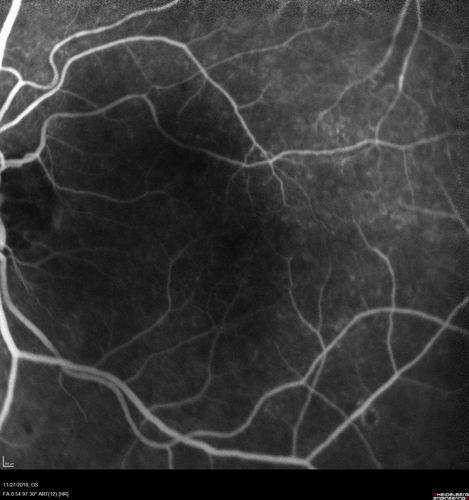

Unusual Intraretinal Deposits

71 year old diabetic man on dialysis with 20/20 vision and intraretinal deposits. Recent 150 lb weight loss, on dialysis, see album properties for full history